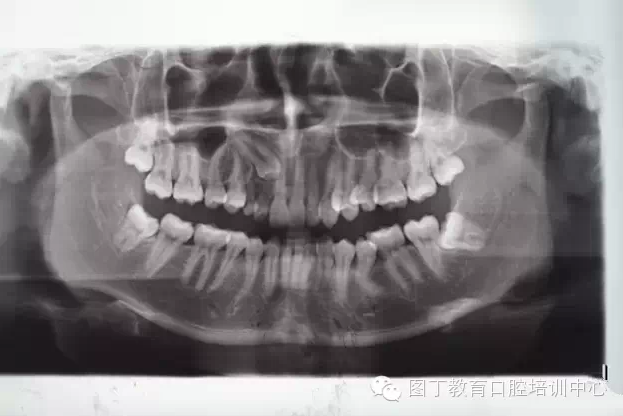

術前全景片檢查:13位于11、12根尖區(qū)。乳Ⅲ滯留。

QQ圖片20150730094928.png